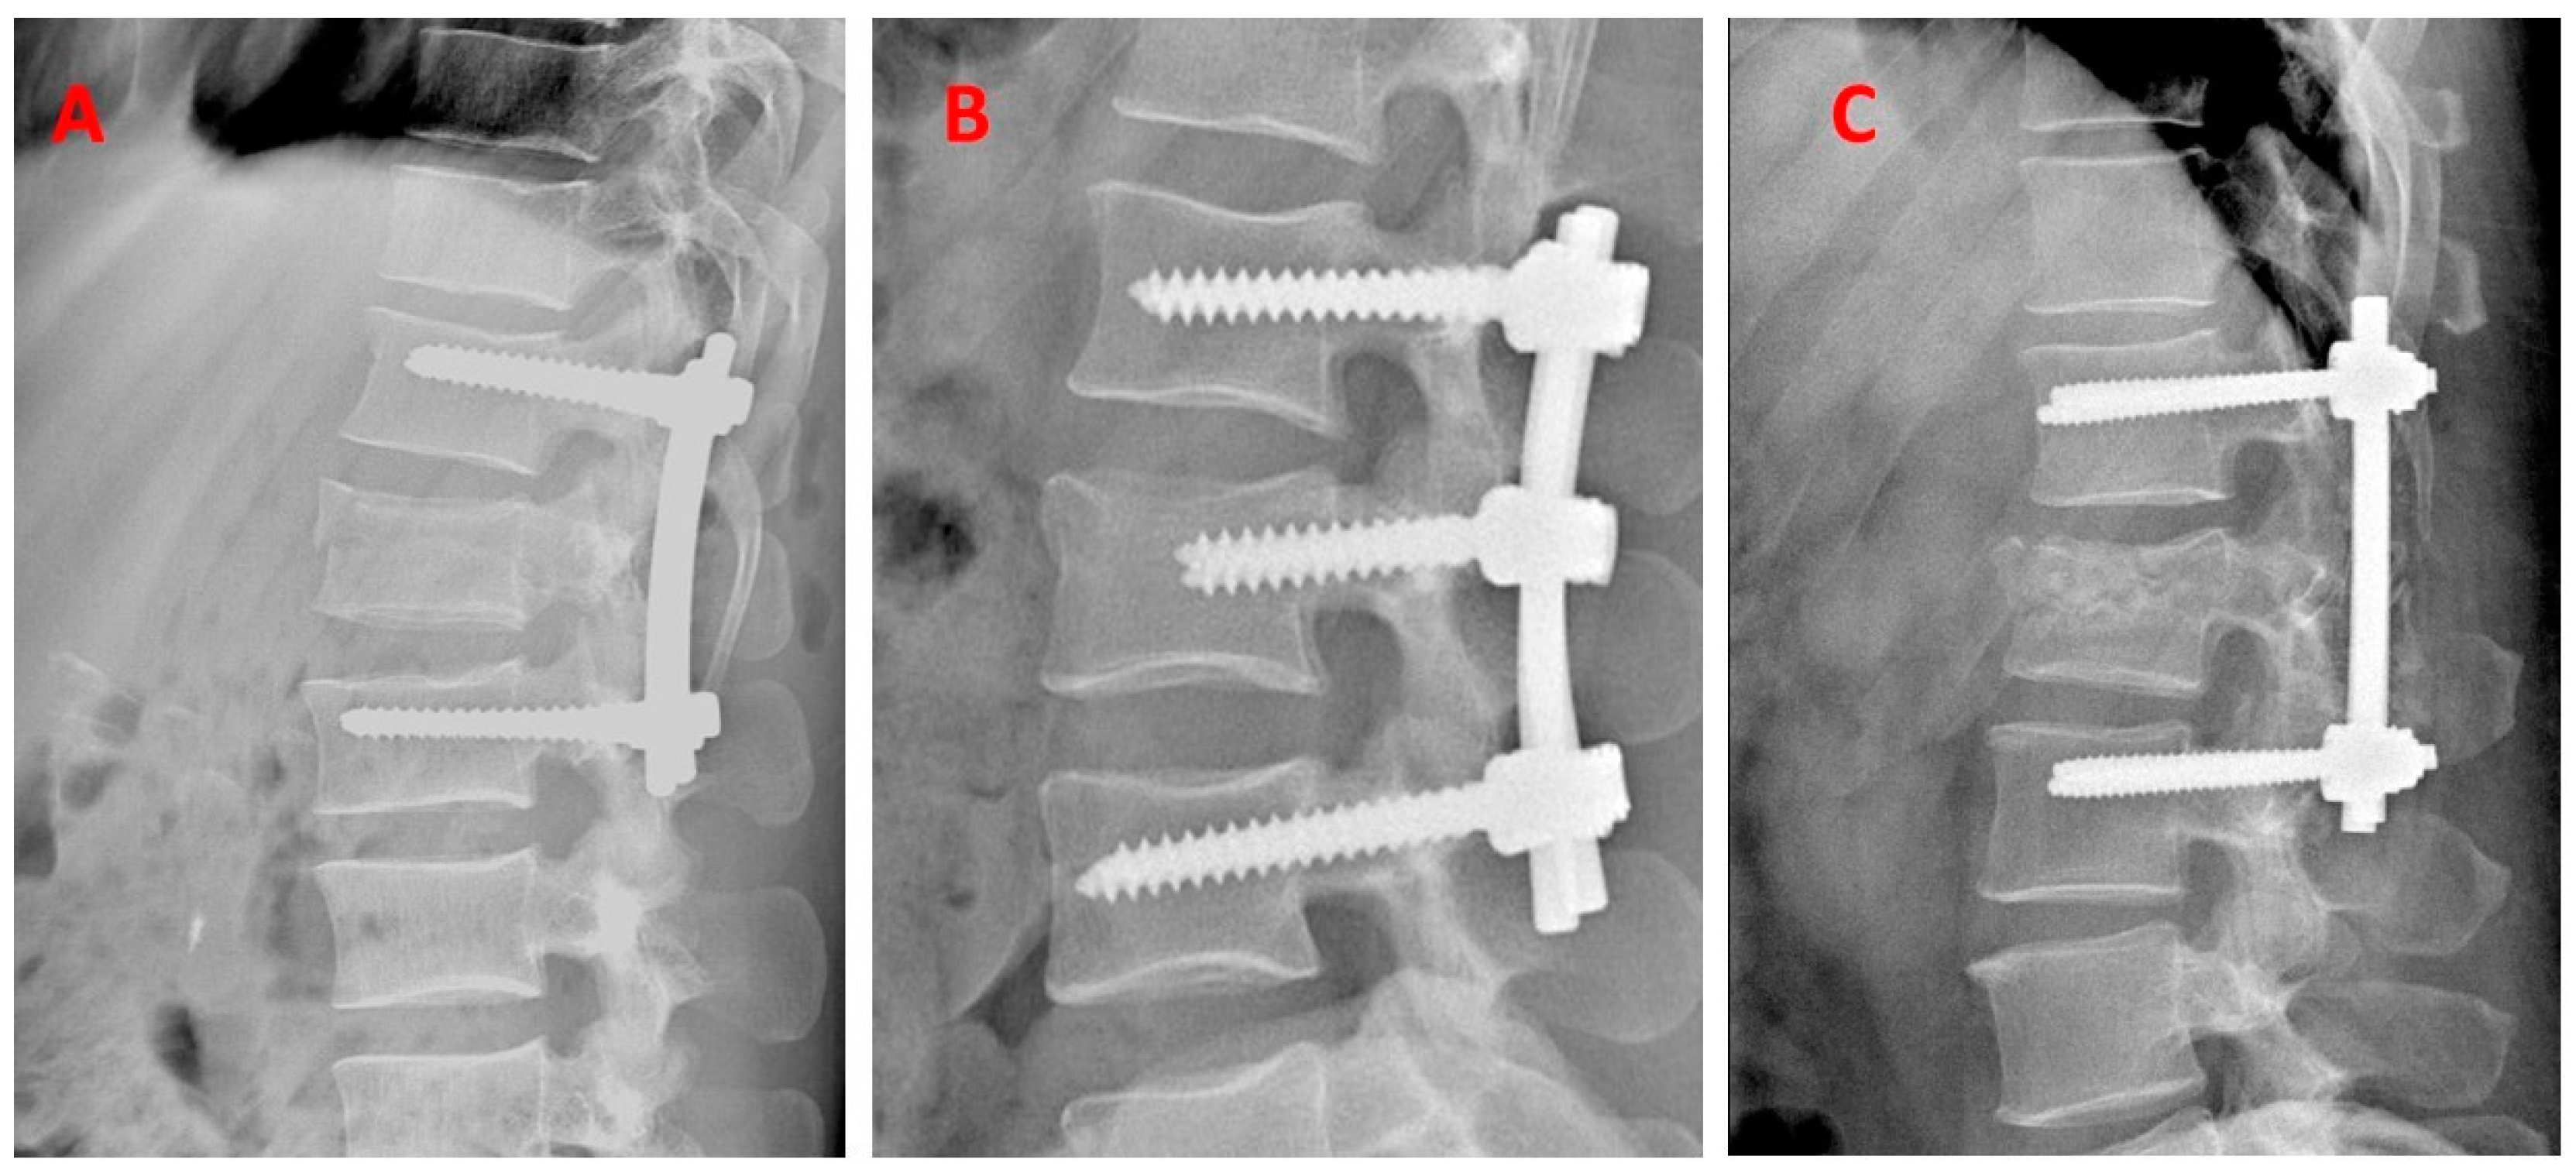

2.3. Surgical Techniques and Procedures

2.3.2. Description of the Surgical Procedure